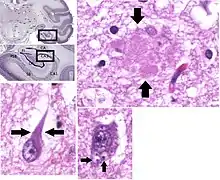

Both Aβ plaques and neurofibrillary tangles are clearly visible by microscopy in brains of those with Alzheimer's disease,[88] especially in the hippocampus.[89] However, Alzheimer's disease may occur without neurofibrillary tangles in the neocortex.[90] Plaques are dense, mostly insoluble deposits of beta-amyloid peptide and cellular material outside and around neurons. Tangles (neurofibrillary tangles) are aggregates of the microtubule-associated protein tau which has become hyperphosphorylated and accumulate inside the cells themselves. Although many older individuals develop some plaques and tangles as a consequence of aging, the brains of people with Alzheimer's disease have a greater number of them in specific brain regions such as the temporal lobe.[91] Lewy bodies are not rare in the brains of people with Alzheimer's disease.[92]

Assessment of intellectual functioning including memory testing can further characterise the state of the disease.[1] Medical organizations have created diagnostic criteria to ease and standardise the diagnostic process for practising physicians. Definitive diagnosis can only be confirmed with post-mortem evaluations when brain material is available and can be examined histologically for senile plaques and neurofibrillary tangles.[119][120]